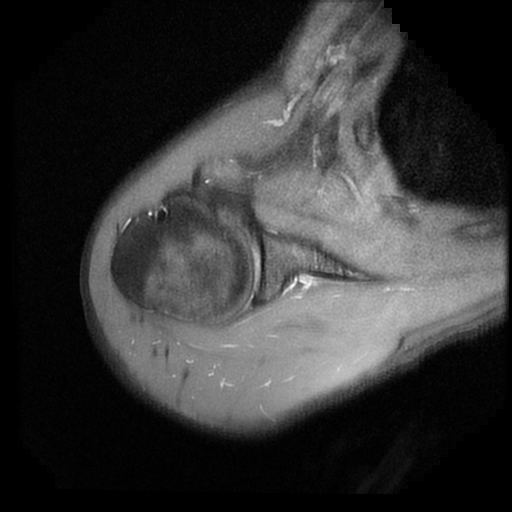

TECNICA EMPLEADA

Se coloca al paciente en decúbito supino, utilizando bobina dedicada de 8 canales, obteniendo imágenes en planos axial, sagital y coronal, secuencias, Spin Echo, Eco de Gradiente, potenciadas a Densidad de Protones, con pulsos de saturación de grasa.

HALLAZGOS IMAGENOLOGICOS

Lesión post traumática de Hill Sachs a nivel de la cabeza humeral, tendinosis aguda del supra espinoso.